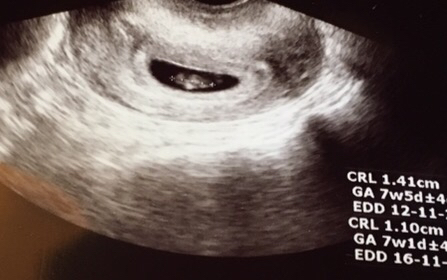

Se on kumminkin niin arpapeliä ja sattuman kauppaa kuka plussaa ja milloin. Omaan plussaan sillon marraskuussa en todellakaan uskonut ja välillä tuntuu etten uskois vieläkään ellei potkuja tulis tasaiseen tahtiin.